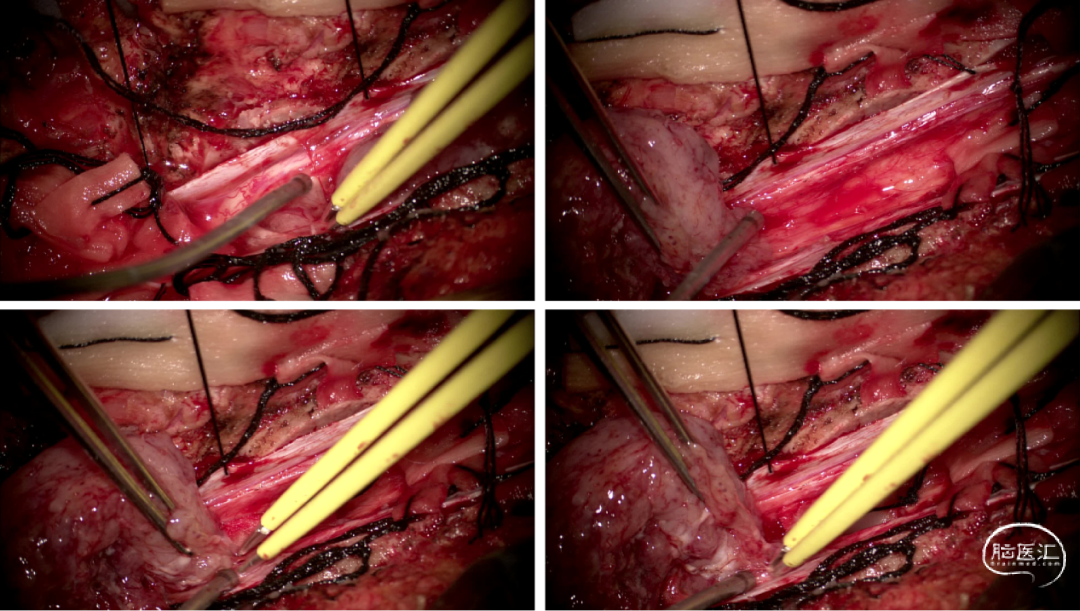

手术情况

硬脊膜张力高,脊髓向背侧膨出,与脊髓腹侧粘连紧密,肿瘤挤压脊髓,肿瘤边界分离,减少对胸髓的牵拉,降低了术后患者神经功能发生的概率,术后患者肢体麻木症状改善。